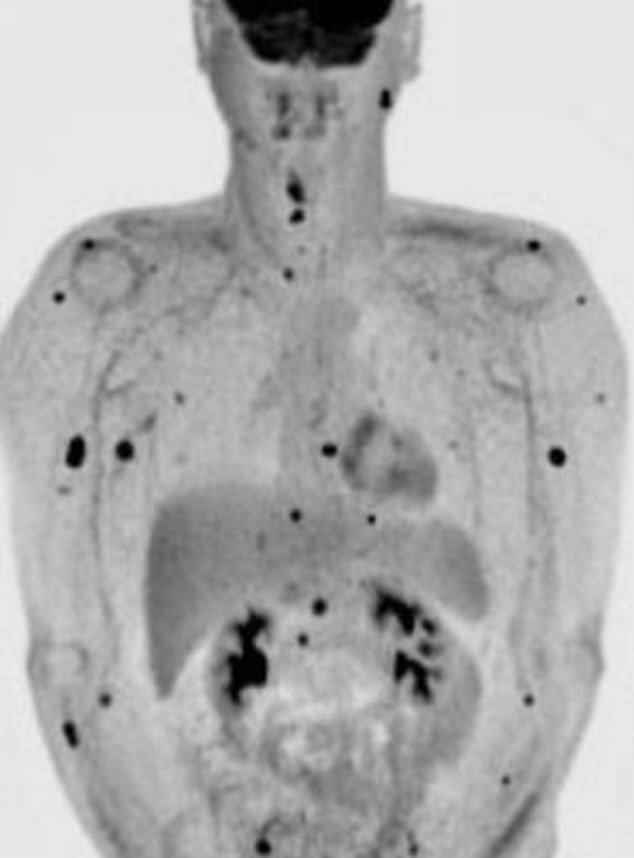

This is known as nodular melanoma and is deemed to be one of the most deadly neoplasms, as revealed by experts. And that’s why he is now left with no choice but to make the most of his life.

After having the mole removed and the lymph nodes associated with it, he noticed another growth behind his ear and it was clear that there was no end. The tumor was spreading.